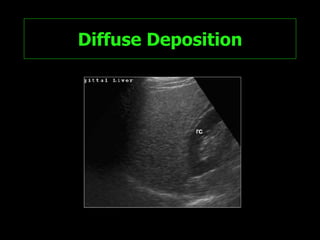

Diffuse Deposition Diffuse fat deposition in the liver is the  most frequently encountered pattern .  Liver involvement usually is  homogeneous . The image interpretation is straightforward if the rules specified earlier are applied

Diffuse Deposition